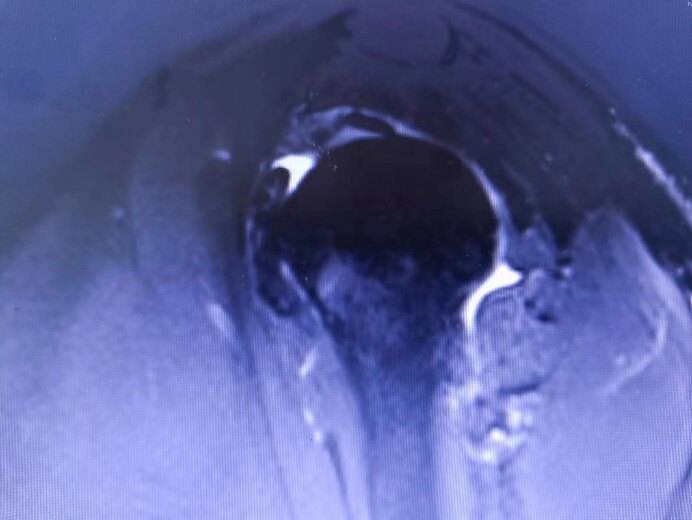

(文|鄭州市骨科醫(yī)院康復(fù)醫(yī)學(xué)科張寧)魏女士,40歲,半年前摔倒后左肩疼痛,后曾至多次至按摩店行按摩治療、曾至診所行理療、美容院行正骨等治療,治療時(shí)感左肩疼痛略減輕,但活動(dòng)后仍明顯疼痛,并出現(xiàn)明顯活動(dòng)受限,前后花費(fèi)一萬(wàn)余元,肩關(guān)節(jié)疼痛無(wú)明顯改善,愈發(fā)嚴(yán)重,影響睡眠及日常生活,夜間嘗嘗痛醒,后至我院住院,完善左肩磁共振檢查發(fā)現(xiàn)左肩關(guān)節(jié)積液,左肩凍結(jié)肩,經(jīng)評(píng)估后,給予對(duì)癥藥物治療,左肩疼痛有所減輕,但夜間仍明顯疼痛,不能患側(cè)臥位,再次給予評(píng)估,給予左肩局部按摩治療,左肩疼痛有所減輕,但仍活動(dòng)受限,患者聽(tīng)聞針灸效果可,要求行針灸,再次行評(píng)估,患者左肩“圓肩”姿態(tài),并功能性“高肩”、“腿短”,左側(cè)肋骨“外翻”,前區(qū)肩關(guān)節(jié)時(shí)肋骨“外翻”加重,考慮為傷后肩部外旋力減弱,內(nèi)收內(nèi)旋力增強(qiáng)致“圓肩”姿態(tài),左側(cè)胸小肌緊張、腹內(nèi)外斜肌疲勞無(wú)力導(dǎo)致肋骨“外翻”,左肩活動(dòng)受限,代償活動(dòng)所致“高肩”及“腿短”,查體見(jiàn):上斜方肌、胸小肌、大小圓肌、腹內(nèi)外斜肌等處壓痛明顯,外旋、外展肌減弱,前屈、內(nèi)收、內(nèi)旋、后伸、水平后伸受限,被動(dòng)活動(dòng)時(shí)肩部疼痛明顯,做外展及后伸時(shí)左側(cè)輕度翼狀肩胛,給予對(duì)應(yīng)部位針灸治療,告知患者注意事項(xiàng),針灸治療第二天患者訴除針灸部位酸痛外,夜間肩關(guān)節(jié)疼痛減輕,患側(cè)臥位已無(wú)明顯疼痛,針灸治療第三天,患者訴針灸部位無(wú)明顯疼痛,指導(dǎo)患者加強(qiáng)前鋸肌訓(xùn)練,左肩活動(dòng)功能明顯改善,被動(dòng)活動(dòng)時(shí)左肩外側(cè)已無(wú)疼痛感,針灸治療一周后雙側(cè)肩關(guān)節(jié)活動(dòng)接近正常,左肩無(wú)疼痛感。治療約3周,復(fù)查左肩磁共振檢查提示左肩已無(wú)明顯異常,患者表示不可思議,感嘆有病還是得到正規(guī)醫(yī)院接受科學(xué)治療,療效快花費(fèi)低??按語(yǔ):肩部外傷或持續(xù)勞損所致的肩關(guān)節(jié)疼痛,多與肩袖損傷與勞損所致,肩袖由岡上肌、岡下肌、肩胛下肌、小圓肌組成,是肩關(guān)節(jié)穩(wěn)定肌,保證肩關(guān)節(jié)固定于肩關(guān)節(jié)內(nèi),若肩部外傷導(dǎo)致肩袖損傷,或勞損導(dǎo)致肩袖肌無(wú)力,都會(huì)導(dǎo)致肩關(guān)節(jié)穩(wěn)定性下降,會(huì)出現(xiàn)肩關(guān)節(jié)結(jié)構(gòu)發(fā)生輕微改變,活動(dòng)時(shí)與周圍組織的摩擦及牽拉則會(huì)導(dǎo)致疼痛,疼痛本身會(huì)導(dǎo)致肩部活動(dòng)受限,若未及時(shí)得到正規(guī)科學(xué)治療,日久出現(xiàn)肩關(guān)節(jié)炎癥滲出,則會(huì)出現(xiàn)靜息痛,炎癥的長(zhǎng)時(shí)間存在,會(huì)刺激滑膜及關(guān)節(jié)囊增厚,則會(huì)出現(xiàn)肩關(guān)節(jié)活動(dòng)進(jìn)一步受限,為保證肩關(guān)節(jié)正常活動(dòng),完成正常日常生活及工作,相關(guān)肌肉持續(xù)參與則會(huì)出現(xiàn)形體上的改變,若持續(xù)未得到糾正則會(huì)出現(xiàn)其他方面的并發(fā)癥,如腰痛及髖關(guān)節(jié)疼痛,有甚至出現(xiàn)踝關(guān)節(jié)及足底疼痛。若出現(xiàn)肩部疼痛不適,及時(shí)至正規(guī)醫(yī)療機(jī)構(gòu)檢查,明確肩部疼痛原因,及時(shí)科學(xué)治療,可快速解決肩部疼痛,改善關(guān)節(jié)功能。